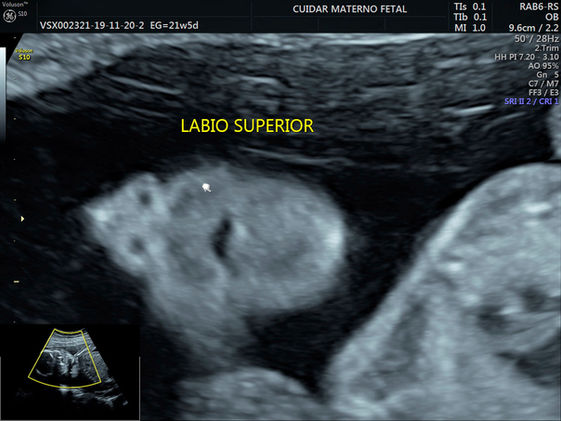

SEGUNDO TRIMESTRE ESTRUCTURAL

Se realiza entre las 18 y 23 semanas

· Cara (ojos, orejas, naríz, labio y paladar)